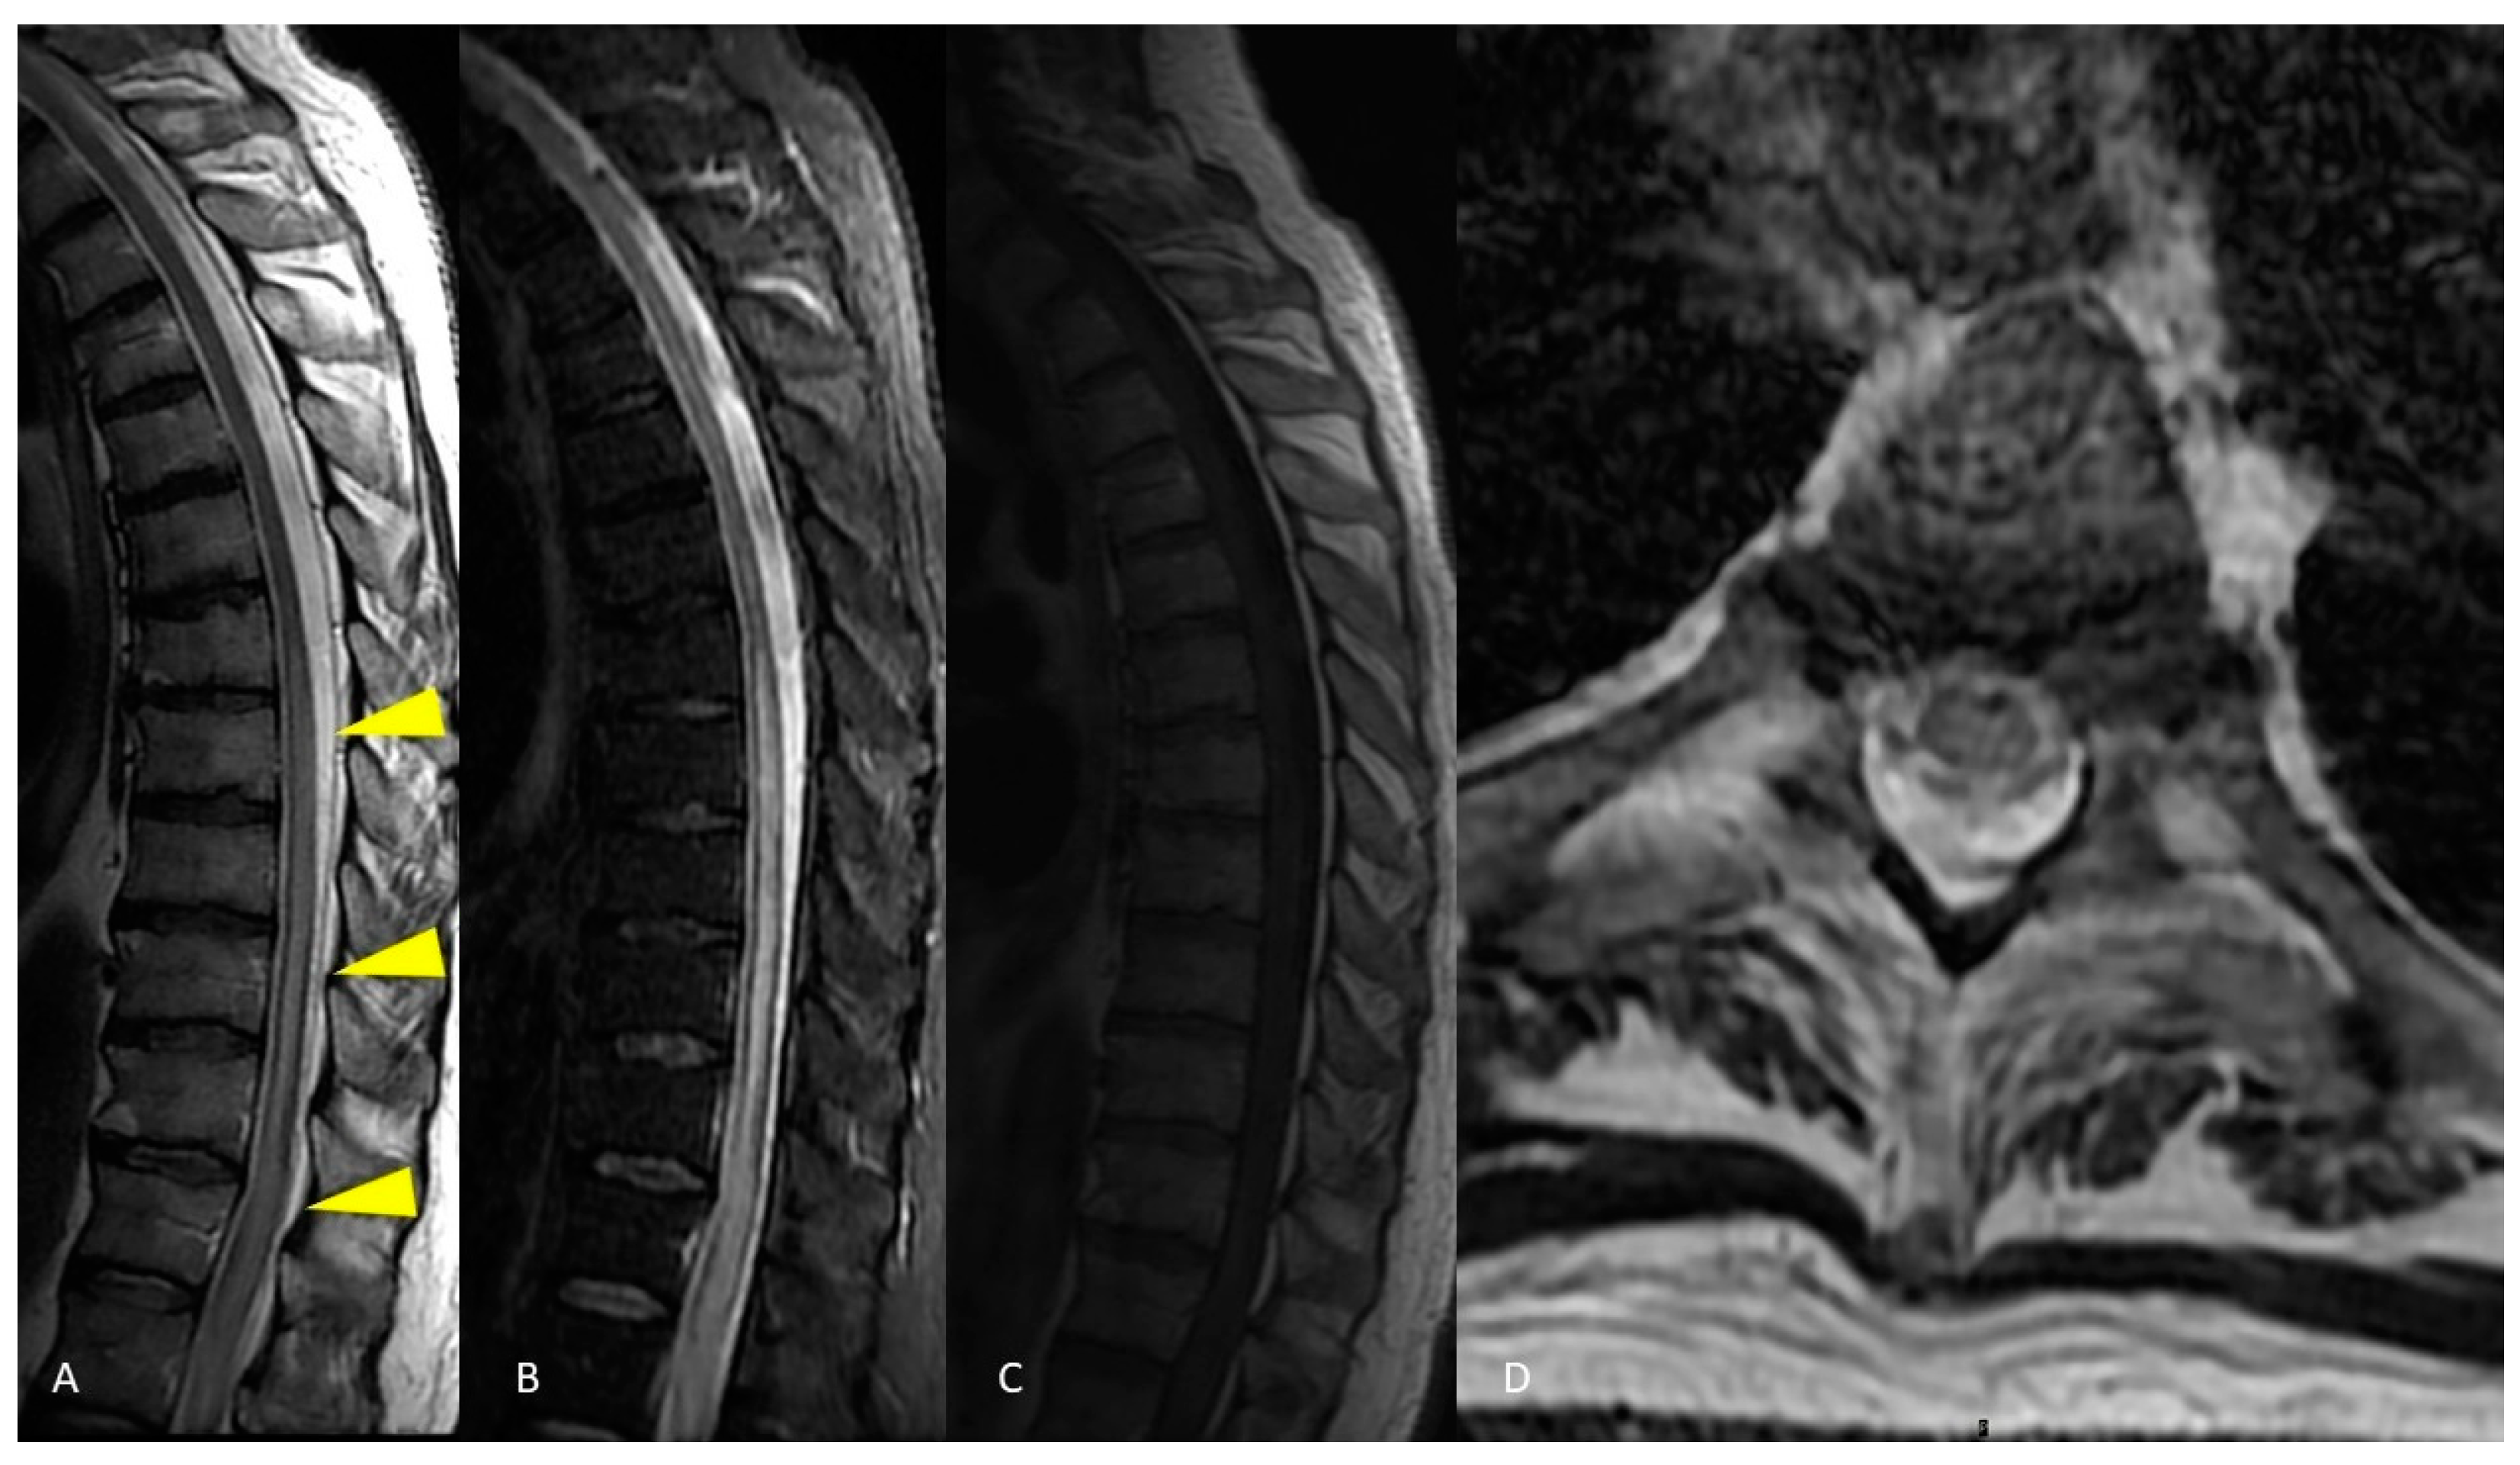

2.1. Case Presentation 1

2.2. Case Presentation 2